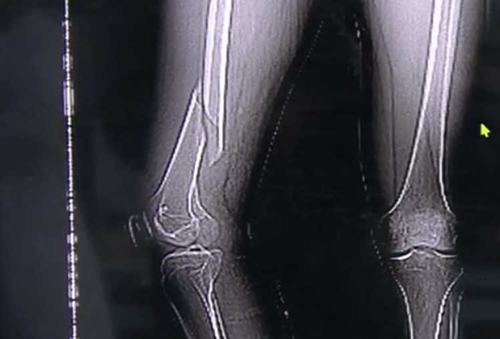

| Chân của anh Vương gãy vì ham mê tập Yoga quá độ. |

Ngay lúc sau, anh nghe thấy một chiếc "cạch" rồi đau nhói ở đùi. Biết đã xảy ra sự cố, anh Vương nén đau vội vàng đến bệnh viện điều trị. Qua kiểm tra, bác sĩ phát hiện xương đùi của anh Vương bị gãy và có rất nhiều huyết khối ở chi dưới.

Bác sĩ tiếp nhận trường hợp của anh Vương cũng cho biết thêm, trường hợp của anh thuộc loại gãy xoắn, vì vậy chọn phương pháp điều trị ít xâm lấn, vết mổ rất nhỏ, bệnh nhân sẽ nhanh chóng hồi phục. Nói chung, chỉ cần được mổ, vào ngày thứ hai sau ca mổ, anh Vương có thể đi lại bằng nạng.